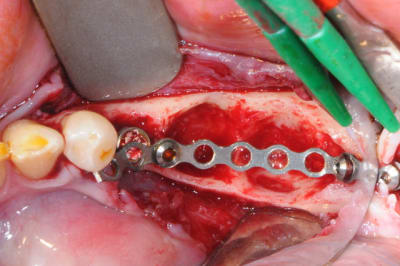

j'en viens maintenant au système FAST de Joseph.

1- les vis et la chaine titane adaptée aux vis.

(pour expliquer: ce système permet de maintenir la chaîne en l'air par sa tête.)

2-3 l'implant 35 que j'ai décidé de garder et donc de nettoyer.

pour le nettoyage, j'ai utilisé, en plus de l'aéropolissage, un écouvillons de chez STRAUMANN en titane.(à mon avis beaucoup trop souple et trop long.

y en a qui connaissent ?)

4-5-6-7 sciage de la mesh titane et positionnement in situ d'un bout à l'autre de l'arcade.

1-2

enfin, mise en place d'une membrane péricarde Jason de 30*50 (je crois)

3- j'ai profité de la stabilité de la mesh comme piquet de tente pour bourrer la cavité avec du MAXGRAFT (os humain)..

4-5- un peu de A-PRF (the king !)

6- le plus important des sutures hermétiques et une gencive immobile en fin d'intervention

7 les radios post-op